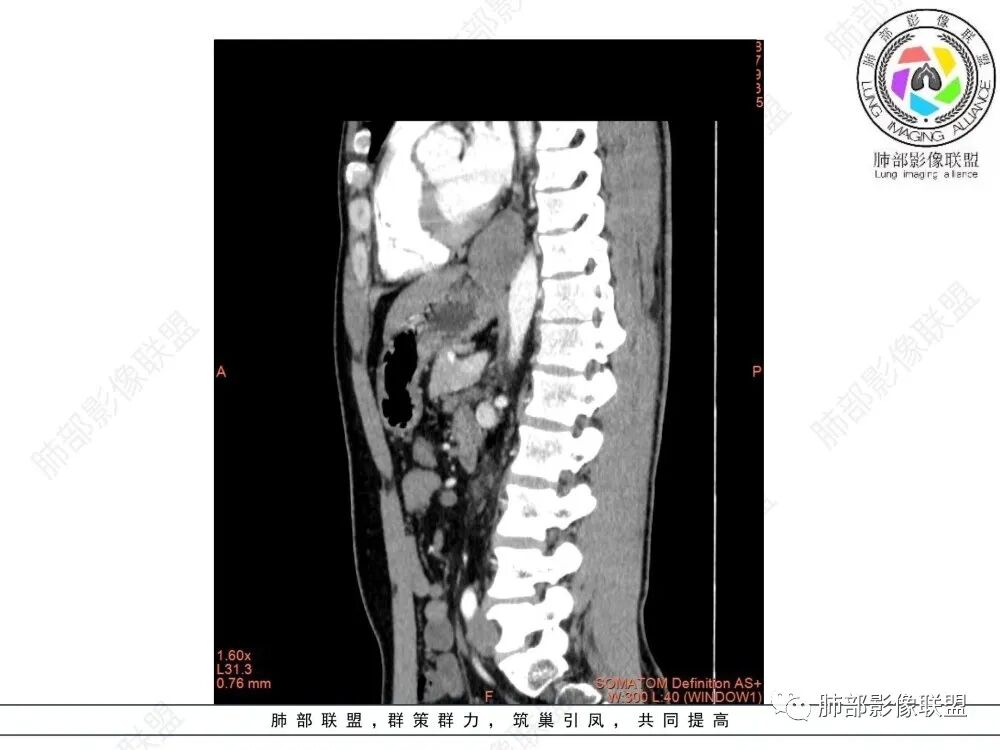

年轻男性,食管下段占位性病变长轴平行于食管,平扫密度尚均匀,增强轻度强化,MRI示T1、T2低信号,DWI低信号。考虑来源于食管,考虑平滑肌瘤或神经鞘瘤>间质瘤

平滑肌瘤(食管下段团块状肿块,环食管生长,分叶密度均匀,增强轻度强化。钡餐时食管受压移位,T1 T2 DWi低信号,病变来源于食管,考虑平滑肌瘤)

T2低信号是关键,提示平滑肌细胞

食管平滑肌瘤是最常见的食管良性肿瘤,多见于男性,男女之比为2.6:1,高发年龄 30~60岁之间与食管癌相比,食管平滑肌瘤 的一个主要特点是病史相对较长,病情进展缓慢。病史最长者达10年余,平均 15.7个月,尽管病史较长,但大多数患者仍能进普食。食管平滑肌瘤的诊断一般比较容易,结合患者临床症状、食管造影及食管镜所见,一般均能得出正确诊断。食管造影主要为充盈缺损,病变与食管壁成锐角,粘膜线连续无破坏,管腔收缩扩张比较自如。钡餐造影敏感性高,但对食管壁间及食管周围情况难以判断。CT具有极高的密度分辨率,并且可以获得高质量的多平面重组图像,有利于食管壁间及食管周围情况的判断,表现为食管下段环绕管壁生长,偏心性或薄厚不均软组织密度肿块,密度均匀,内缘分叶状,管腔与正常食管壁构成不规则多角形扩张,增强动脉期无强化,多角度重建其病灶长轴与食管长轴不一致。由于食管壁在收缩状态下厚度约为5.6mm,扩张状态厚度不超过3mm,CT扫描时保持食管处于扩张状态可提高小病灶检出率。MR表现为T1加权等信号,T2加权稍高信号,可见高信号粘膜层,增强扫描轻度渐进性强化,密度均匀,无出血坏死。对于粘膜及周围脂肪间隙的判断具有明显优势。